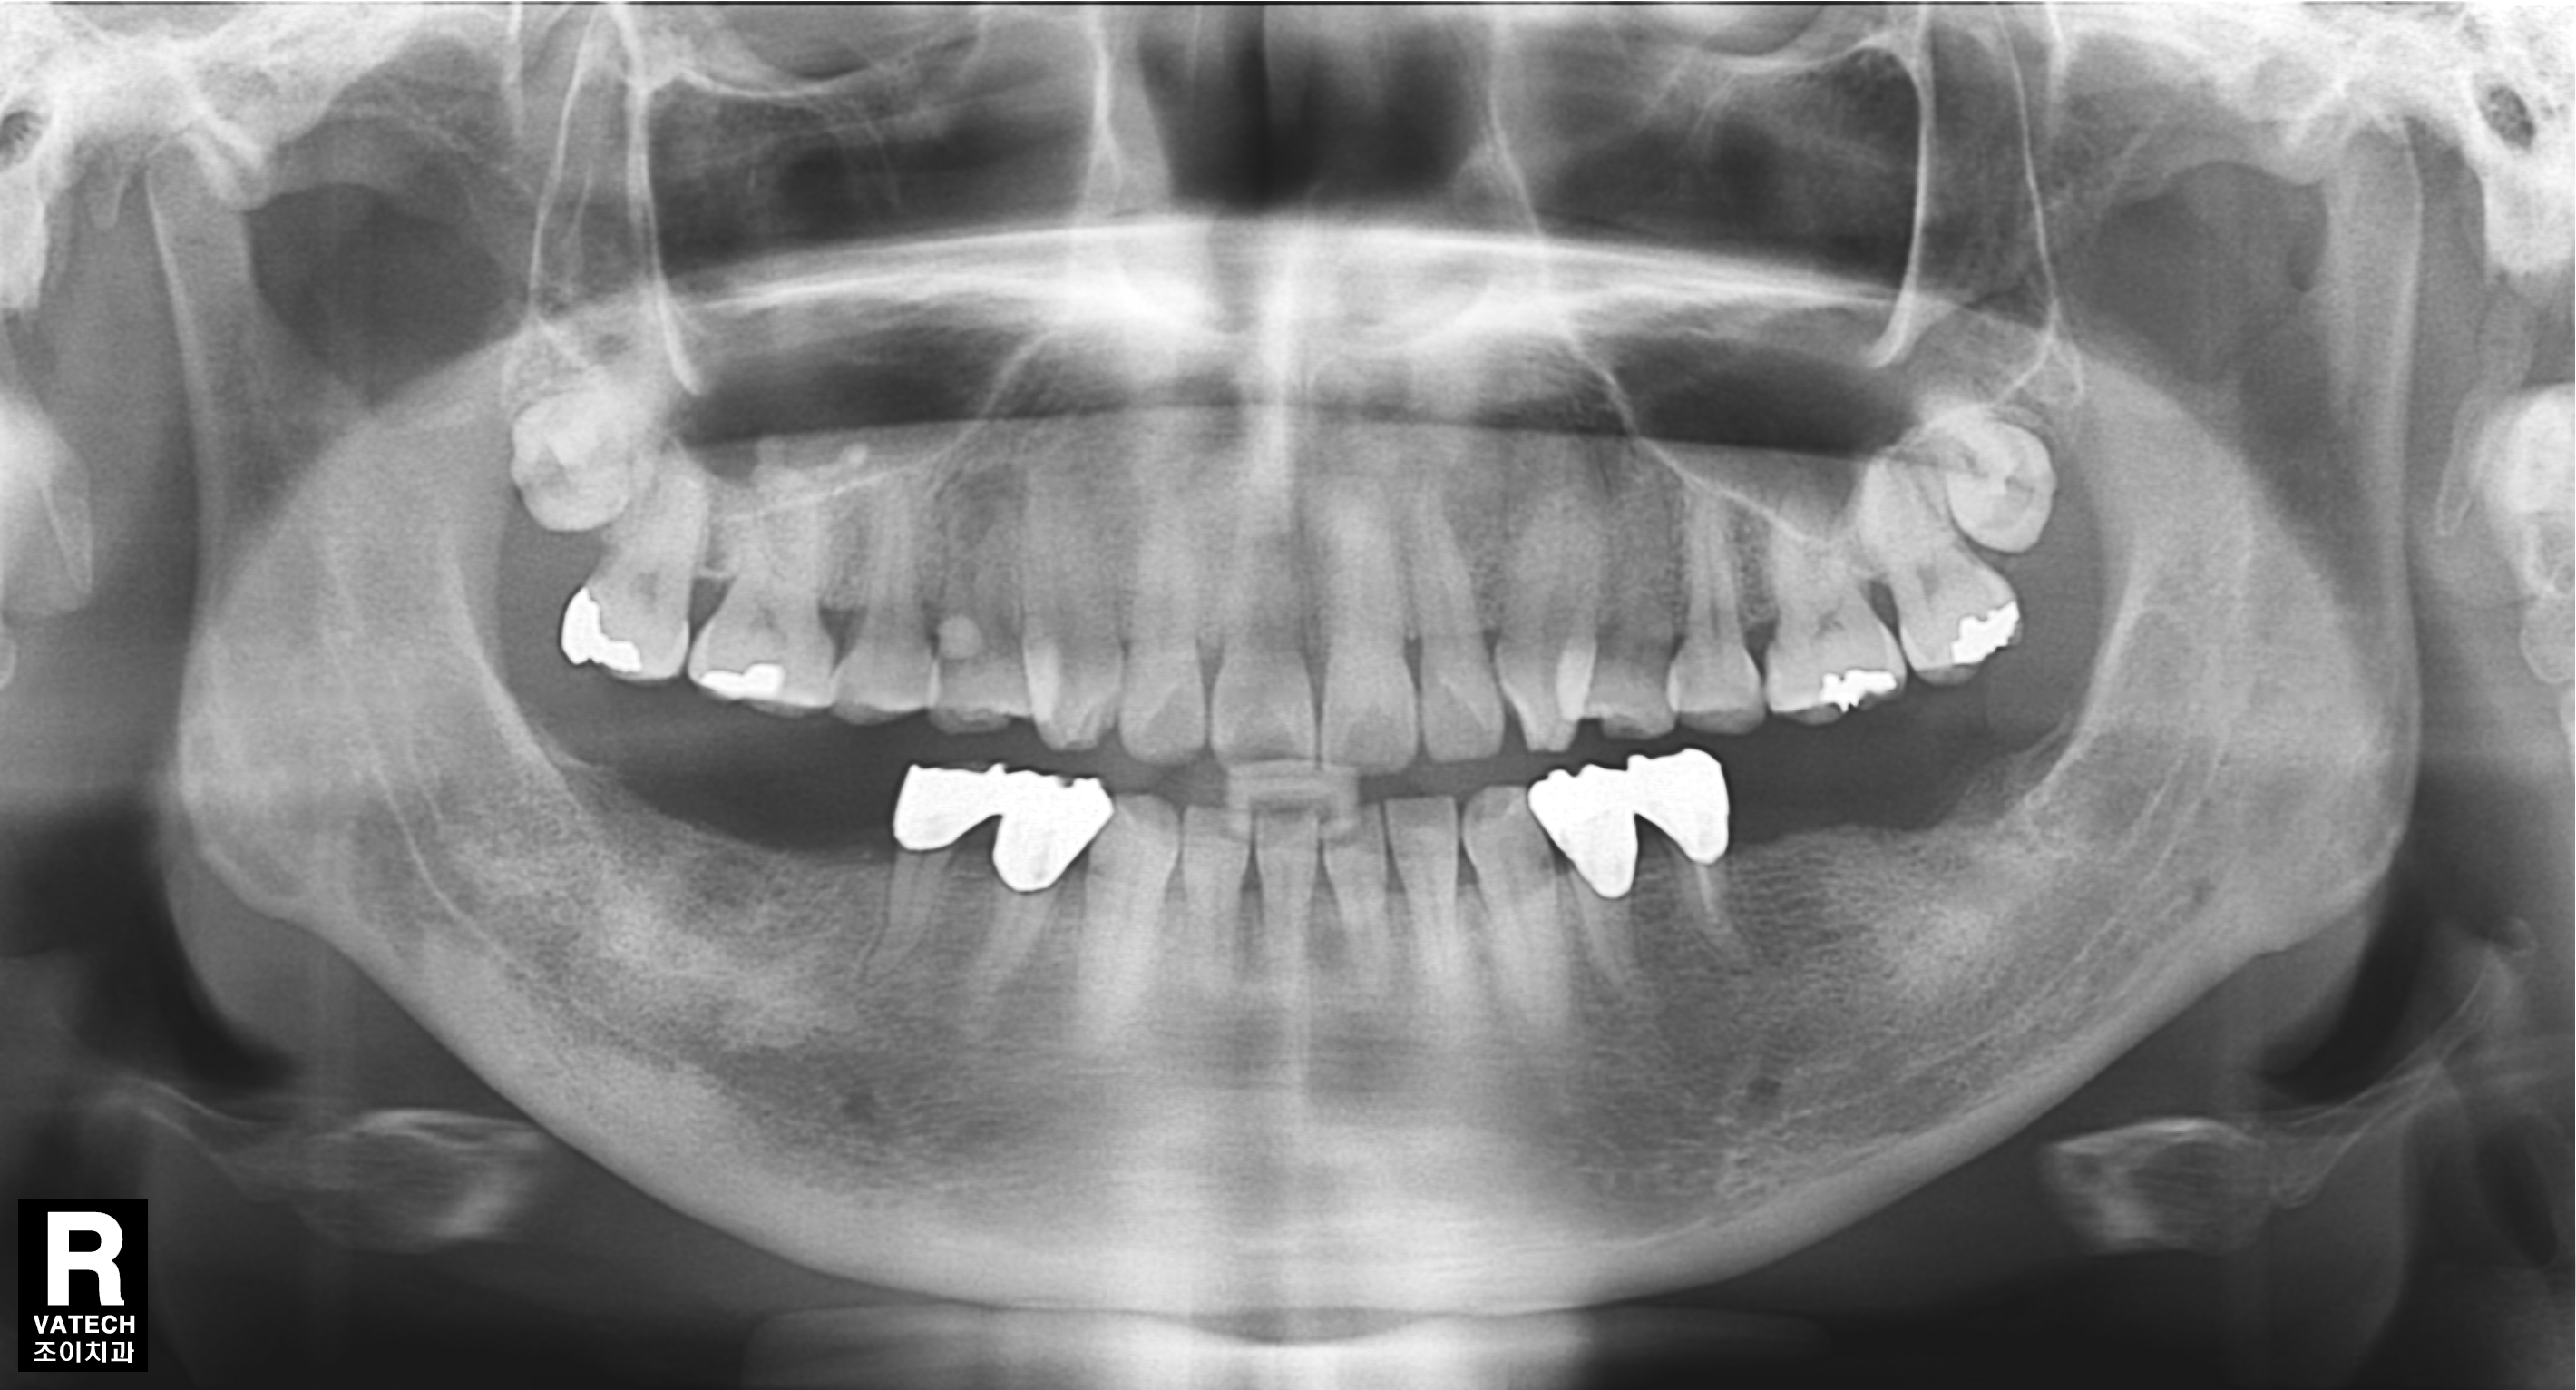

[임플란트] 제목 : 틀니 사용중, 임플란트로 교체하기

하악틀니 사용 중 불편감으로 임플란트로 교체한 예